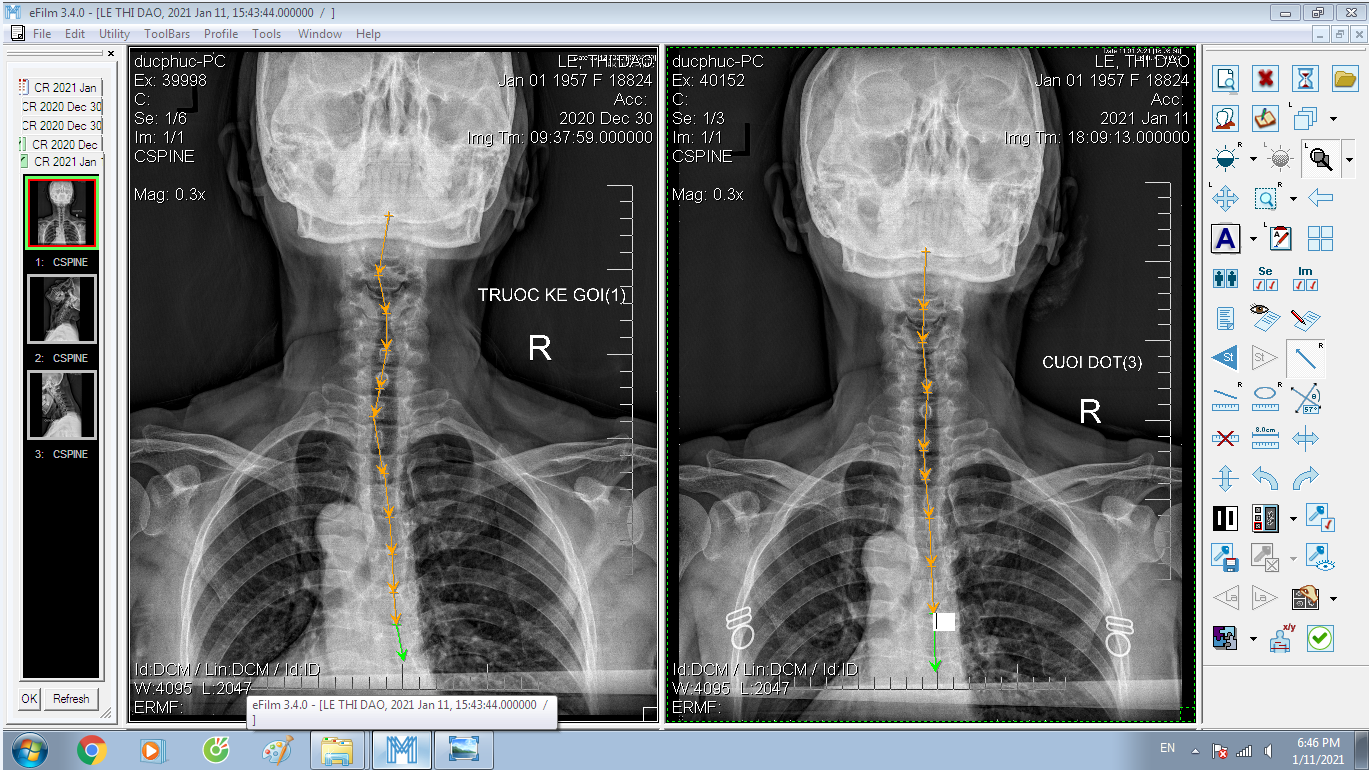

DOCTORLOAN đã thành công trong điều chỉnh xương khớp về đúng vị trí trong thời gian ngắn